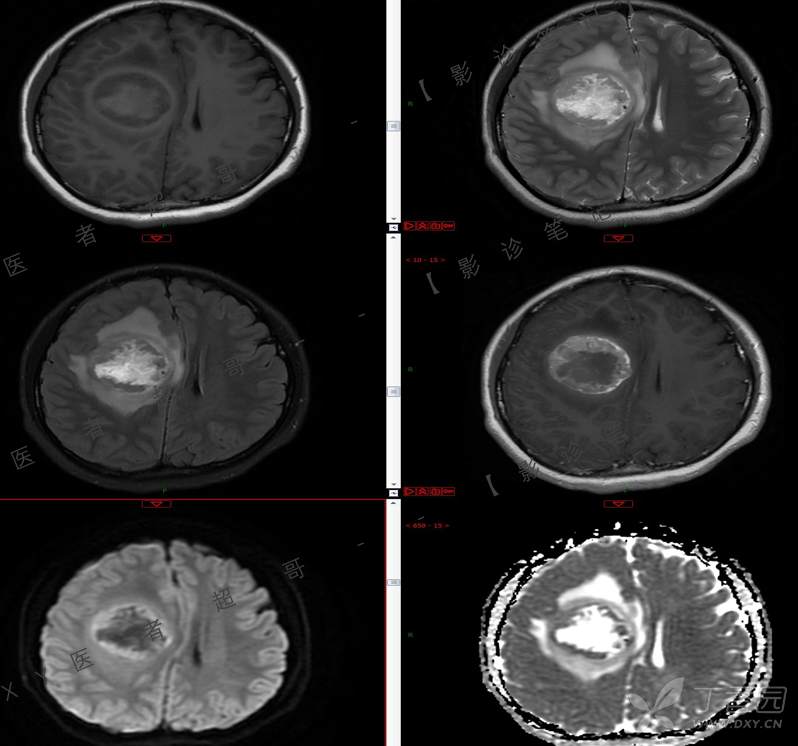

15岁少年,头痛10天,加重伴恶心、呕吐2天,究竟为何?回帖即可查阅病理。

患者年龄:15岁

主 诉:头痛10天,加重伴恶心、呕吐2天。

现病史:患者10天前无明显诱因出现头痛,间断发作,无恶心、呕吐,无肢体抽搐等,于当地医院就诊,体温37.4度,予以对症治疗,具体不详,后症状缓解,2天前患者上述症状较前加重,并感双眼胀痛及视物模糊,伴恶心、呕吐,呕吐数次,为胃内容物,再次于当地医院就诊,行颅脑CT考虑“右侧额顶叶病变”,现为求进一步治疗来我院急诊就诊,以“脑脓肿?”收入我科。患者病来精神差,饮食、睡眠欠佳,体重无明显变化。